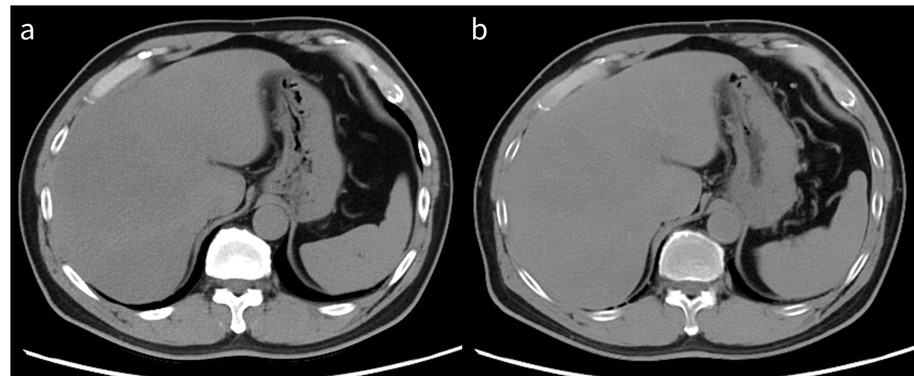

RevolutionApexElite_Gifu02_03.jpg

図2 診断確信度向上例

a: 70 keV仮想単色X線画像

b: 40 keV仮想単色X線画像

膵頭部癌のコントラストは40 keV仮想単色X線画像で優れ(→)、

keVを変えることで診断確信度が向上する場合がある。